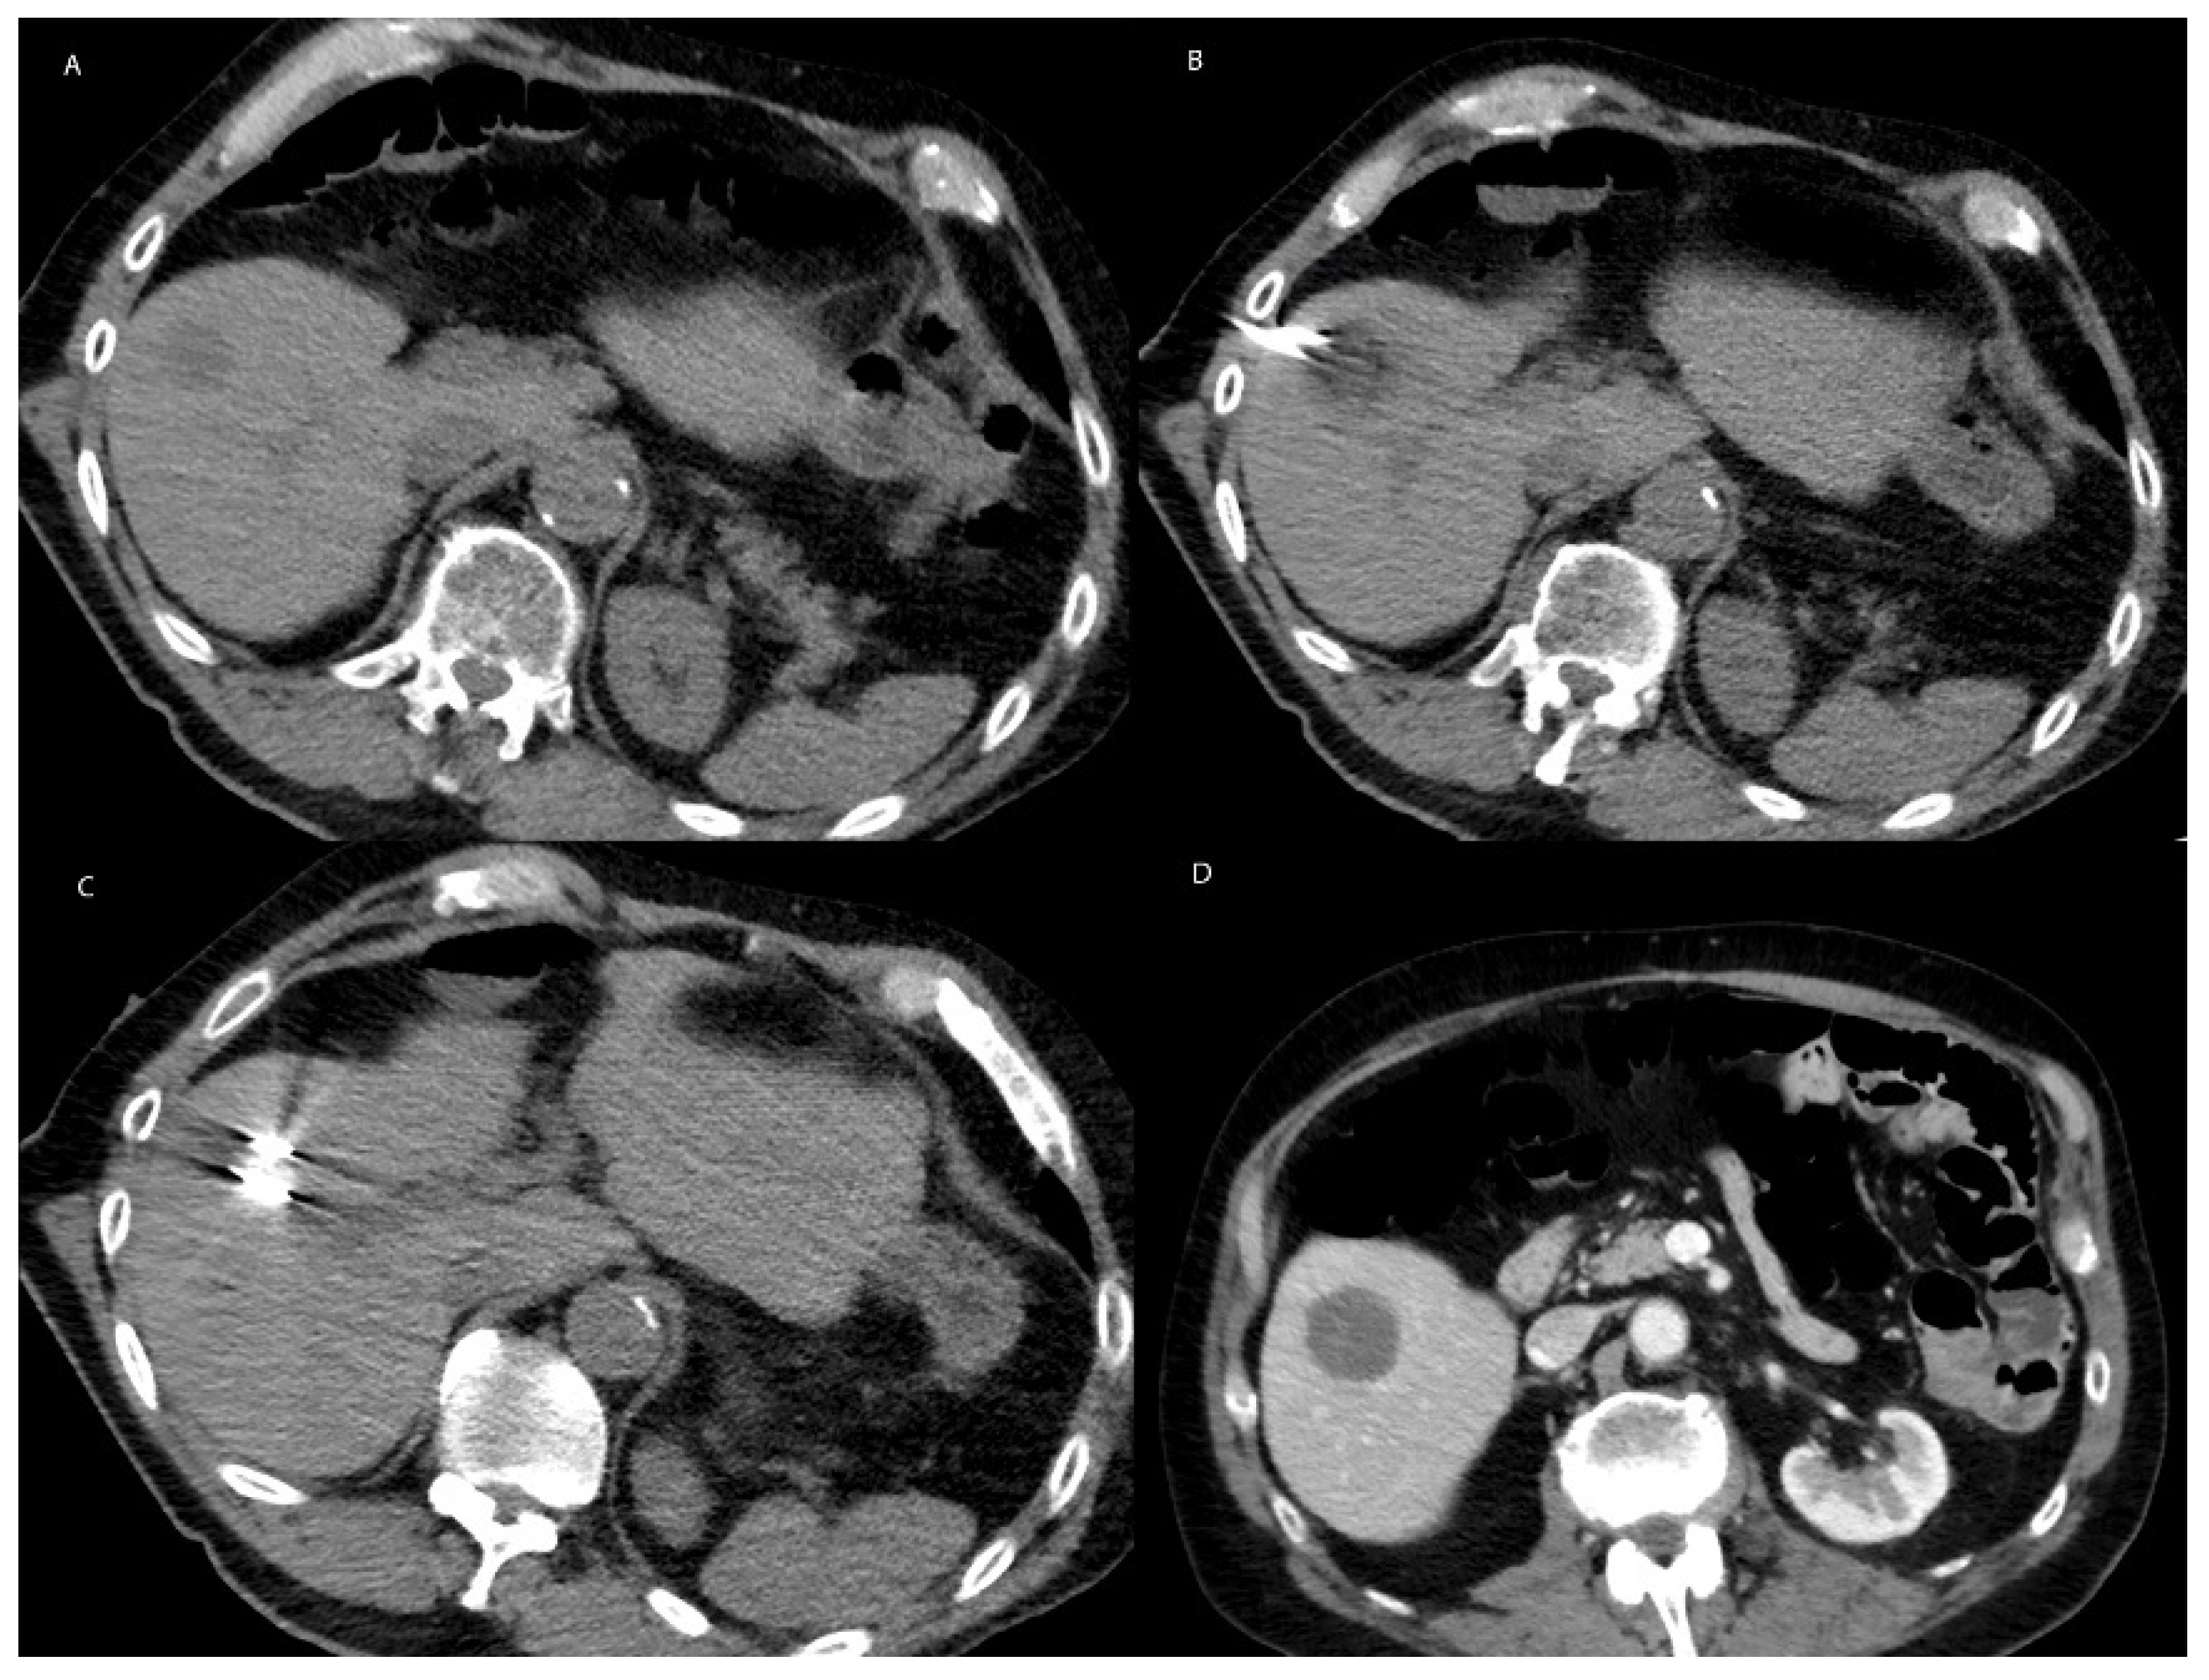

6.1. Technique

6.2. Microwave Ablation in Non-HCC Primary Liver Malignancy

6.3. Microwave Ablation in Metastatic Disease to the Liver